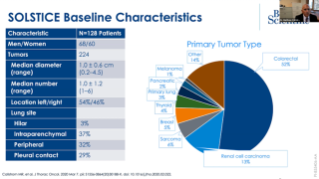

Advancing the Science in Lung Cryoablation

Aug 25, 2020

External Link( 26.0 MB )

Dr Matthew Callstrom speaks about the results from the SOLSTICE study which evaluate the safety and efficacy of cryoablation to treat pulmonary metastatic disease.